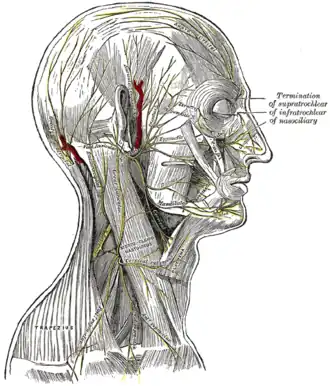

The nerves of the scalp, face, and side of neck.

The nerves of the scalp, face, and side of neck. -